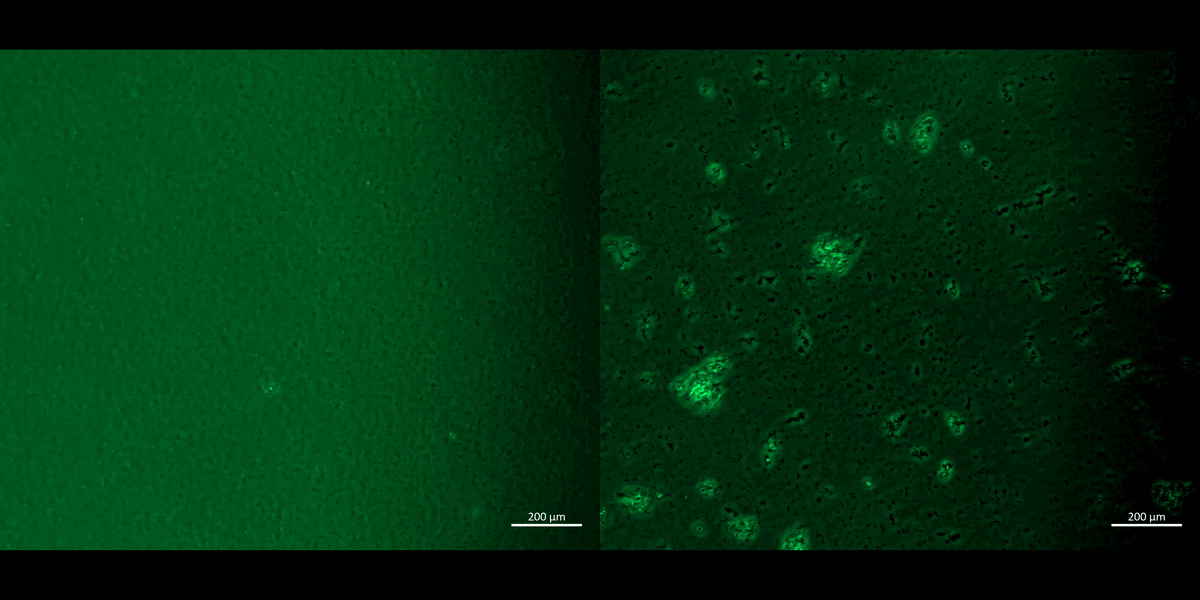

Figure 1: Recap of our study: bioinspired engineering on a kidney-on-a-chip to recapitulate biomarkers of renal calcification. A) Repurposing a kidney-on-a-chip instrument for renal patient-derived macrophage M1 and M2 proliferation on the top and bottom channels of the organ-chip instrument. B) a-c: The confluence of the macrophage cell lines was well supported on the organ chip instrument surface and on the tissue-culture plates: the cluster-forming cells are motile. Apoptotic assays were conducted on a chip and a plate to emulate bioinspired oxidative stress to observe the expression of the biomarkers of prolyl hydroxylase domain 2 (PHD2) and CellRox dye (orange and green, respectively). The morphology of the cells dramatically changed from miniature, motile M1 and M2 variants to aggregated cell clumps emitting PHD2 and CellRox under hypoxia. Image credit: Author’s own.

The transcriptomics outcomes and our pathological pathways of interest corroborated our first-in-study functional assays of inducing hypoxia on a chip. We carried out the experiments by chemically inducing ischemia on M1 and M2 macrophage cell cultures in the presence of sodium dithionite and oxygen glucose deprived buffer, to facilitate oxidative stress on a chip, and observed the expression of redox biomarkers (Figure 13, Movie 2) [Jeewandara 2023]. As discussed in depth, hypoxia response via the hypoxia inducible factor 1α (HIF1α) activation is another key pathway often upregulated in the transcriptome of stone-forming patients to provide a core mechanism of HIF1α stabilization under hypoxia, to drive renal calcification (Figure 13) [Saenz-Medina 2022].

Figure 13: The KEGG meta-data and genomes of four key pathological cascades, including the oxidative stress pathway, hypoxia response via hypoxia inducible factor1α, chemokine signaling, and cell cytotoxicity linked to cell apoptosis during nephrolithiasis, obtained via the GO databases. The omics data support our functional assays of chemically induced apoptosis of M1 and M2 on a chip and a plate, incubated with a redox dye (CellRox), to show the uptake of the oxidative antibody during assays of apoptosis driven cell death (20 x magnification). Image credit: [Jeewandara 2023].

Movie 2: Apoptosis assays on a chip/plate (fluorescence imaging): the M1 and M2 macrophage cell types were incubated with CellRox redox dye and subjected to chemical ischemia-induced redox, to observe the transition from healthy motile cells (left) to fluorescent cell clumps or aggregates (right), to indicate apoptosis or cell death under ischemia, on a 35 mm tissue culture plate. The fluorescent redox dye emission (AG520) uptake indicated oxidative stress driven cell apoptosis (20 x magnification). Image credit: Author’s own [Jeewandara 2023].